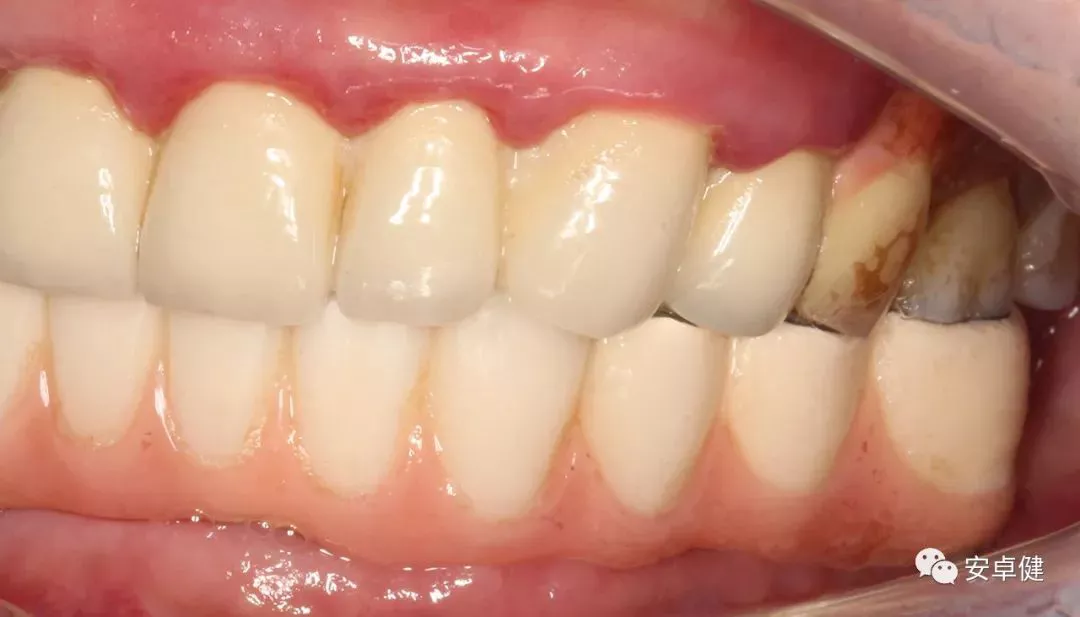

最终修复体侧面咬合照

• 于口内试戴原厂纯钛切削一体式桥架,并检查前牙排蜡外形及后牙咬合关系;

• 聚合瓷烤塑制作最终修复体;

• 为减少牙面磨耗,于后牙区制作360度防裂纯钛金属带;

• 试戴满意后,二级螺丝加力至15N;

• 特氟龙封闭螺丝孔,光固化复合树脂封闭上方螺丝通道,完成最终固定式种植义齿修复;

• 修复体外形能够正确恢复面下1/3高度及侧貌;

• 患者可获得较为稳定的咬合关系,并满足其咀嚼功能的需求;

• 患者42、46部位牙龈退缩,缺乏足够的角化龈,为方便后期清洁维护,选择穿龈较高的龈上肩台;

• 口内观察,修复体边缘金属基台颜色暴露,但由于其处于下颌后牙非微笑暴露区,故对临床整体美观效果的影响在患者可接受范围内。